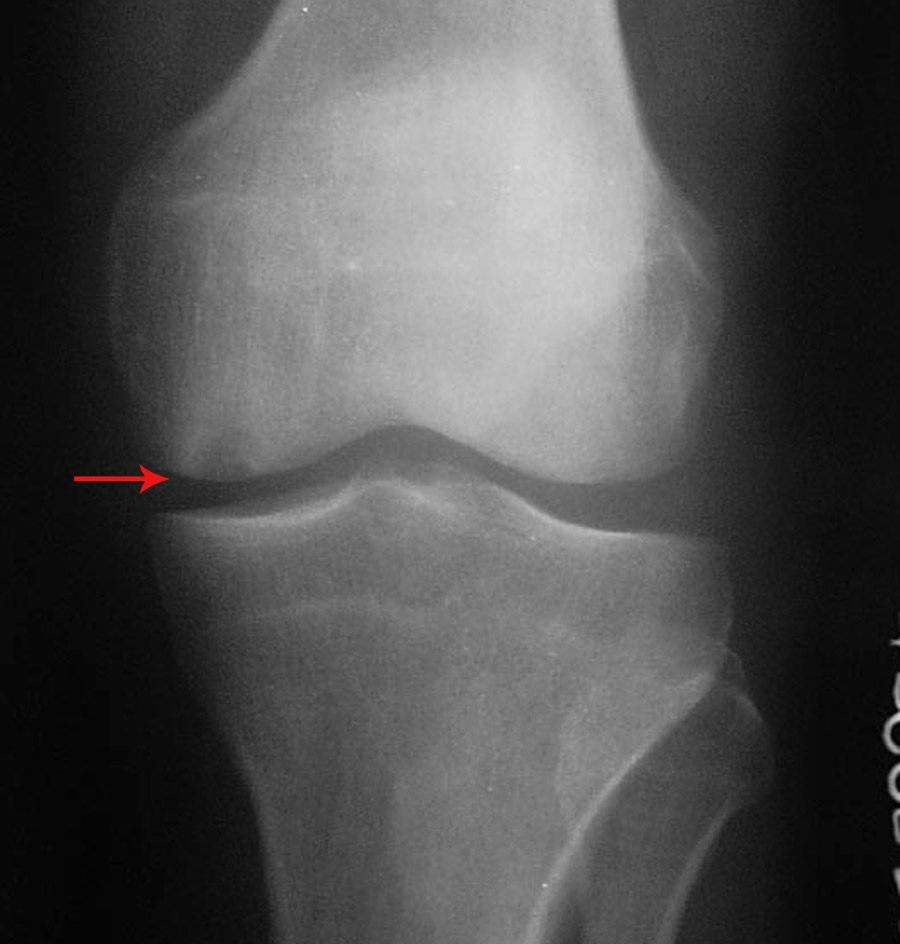

2.左股骨内侧髁下(关节面)局限性骨质密度减低区,性质?加上关节软组织肿胀,最好作进一步检查(mri)。

2左股骨内侧髁下(关节面)局限性骨质密度减低区考虑剥脱性骨炎,建议mri检

左股骨下内侧髁剥脱性骨炎。

左股骨内侧髁病变不排除剥脱性骨炎,必要时mri

考虑:1、左侧股骨内髁剥脱性骨软骨炎;

2、髌骨前上缘骨刺。